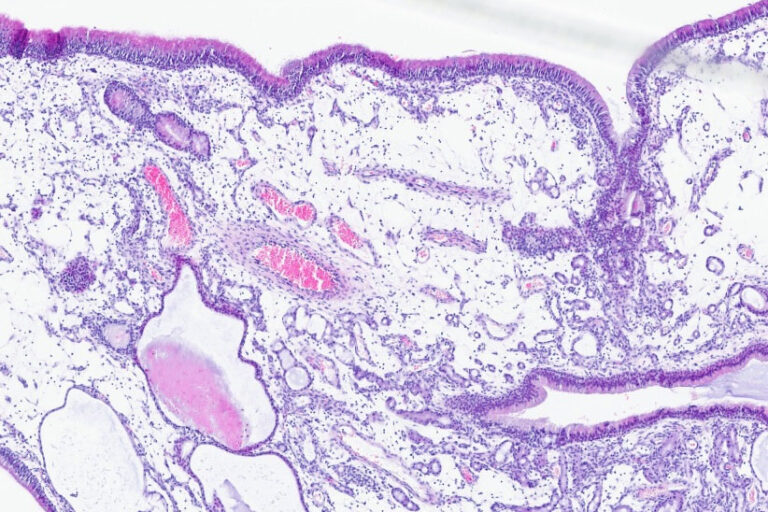

Histologie eines nasalen Polypen eines Hundes, 4er Vergrößerung, HE-Färbung

Wenn die Nase ständig läuft – chronischer Nasenausfluss bei Hund und Katze

LABOKLIN aktuell16. März 2026

Chronischer Nasenausfluss bei Hund und Katze: Diagnostik, Differentialdiagnosen von Rhinitis über Mykosen zu Neoplasien